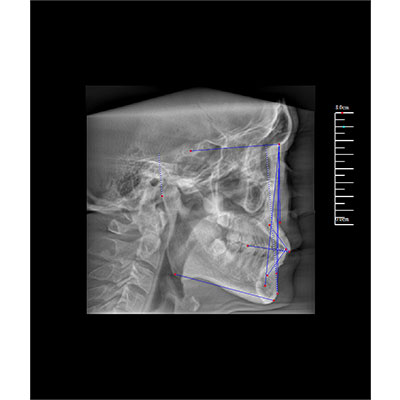

專有三維重建算法,可提供任意位置高清斷層影像。

通過三維容積影像,提取高清口腔全景影像。

可同時觀察軸向面、冠狀面和矢狀面圖像,方便臨床診斷。